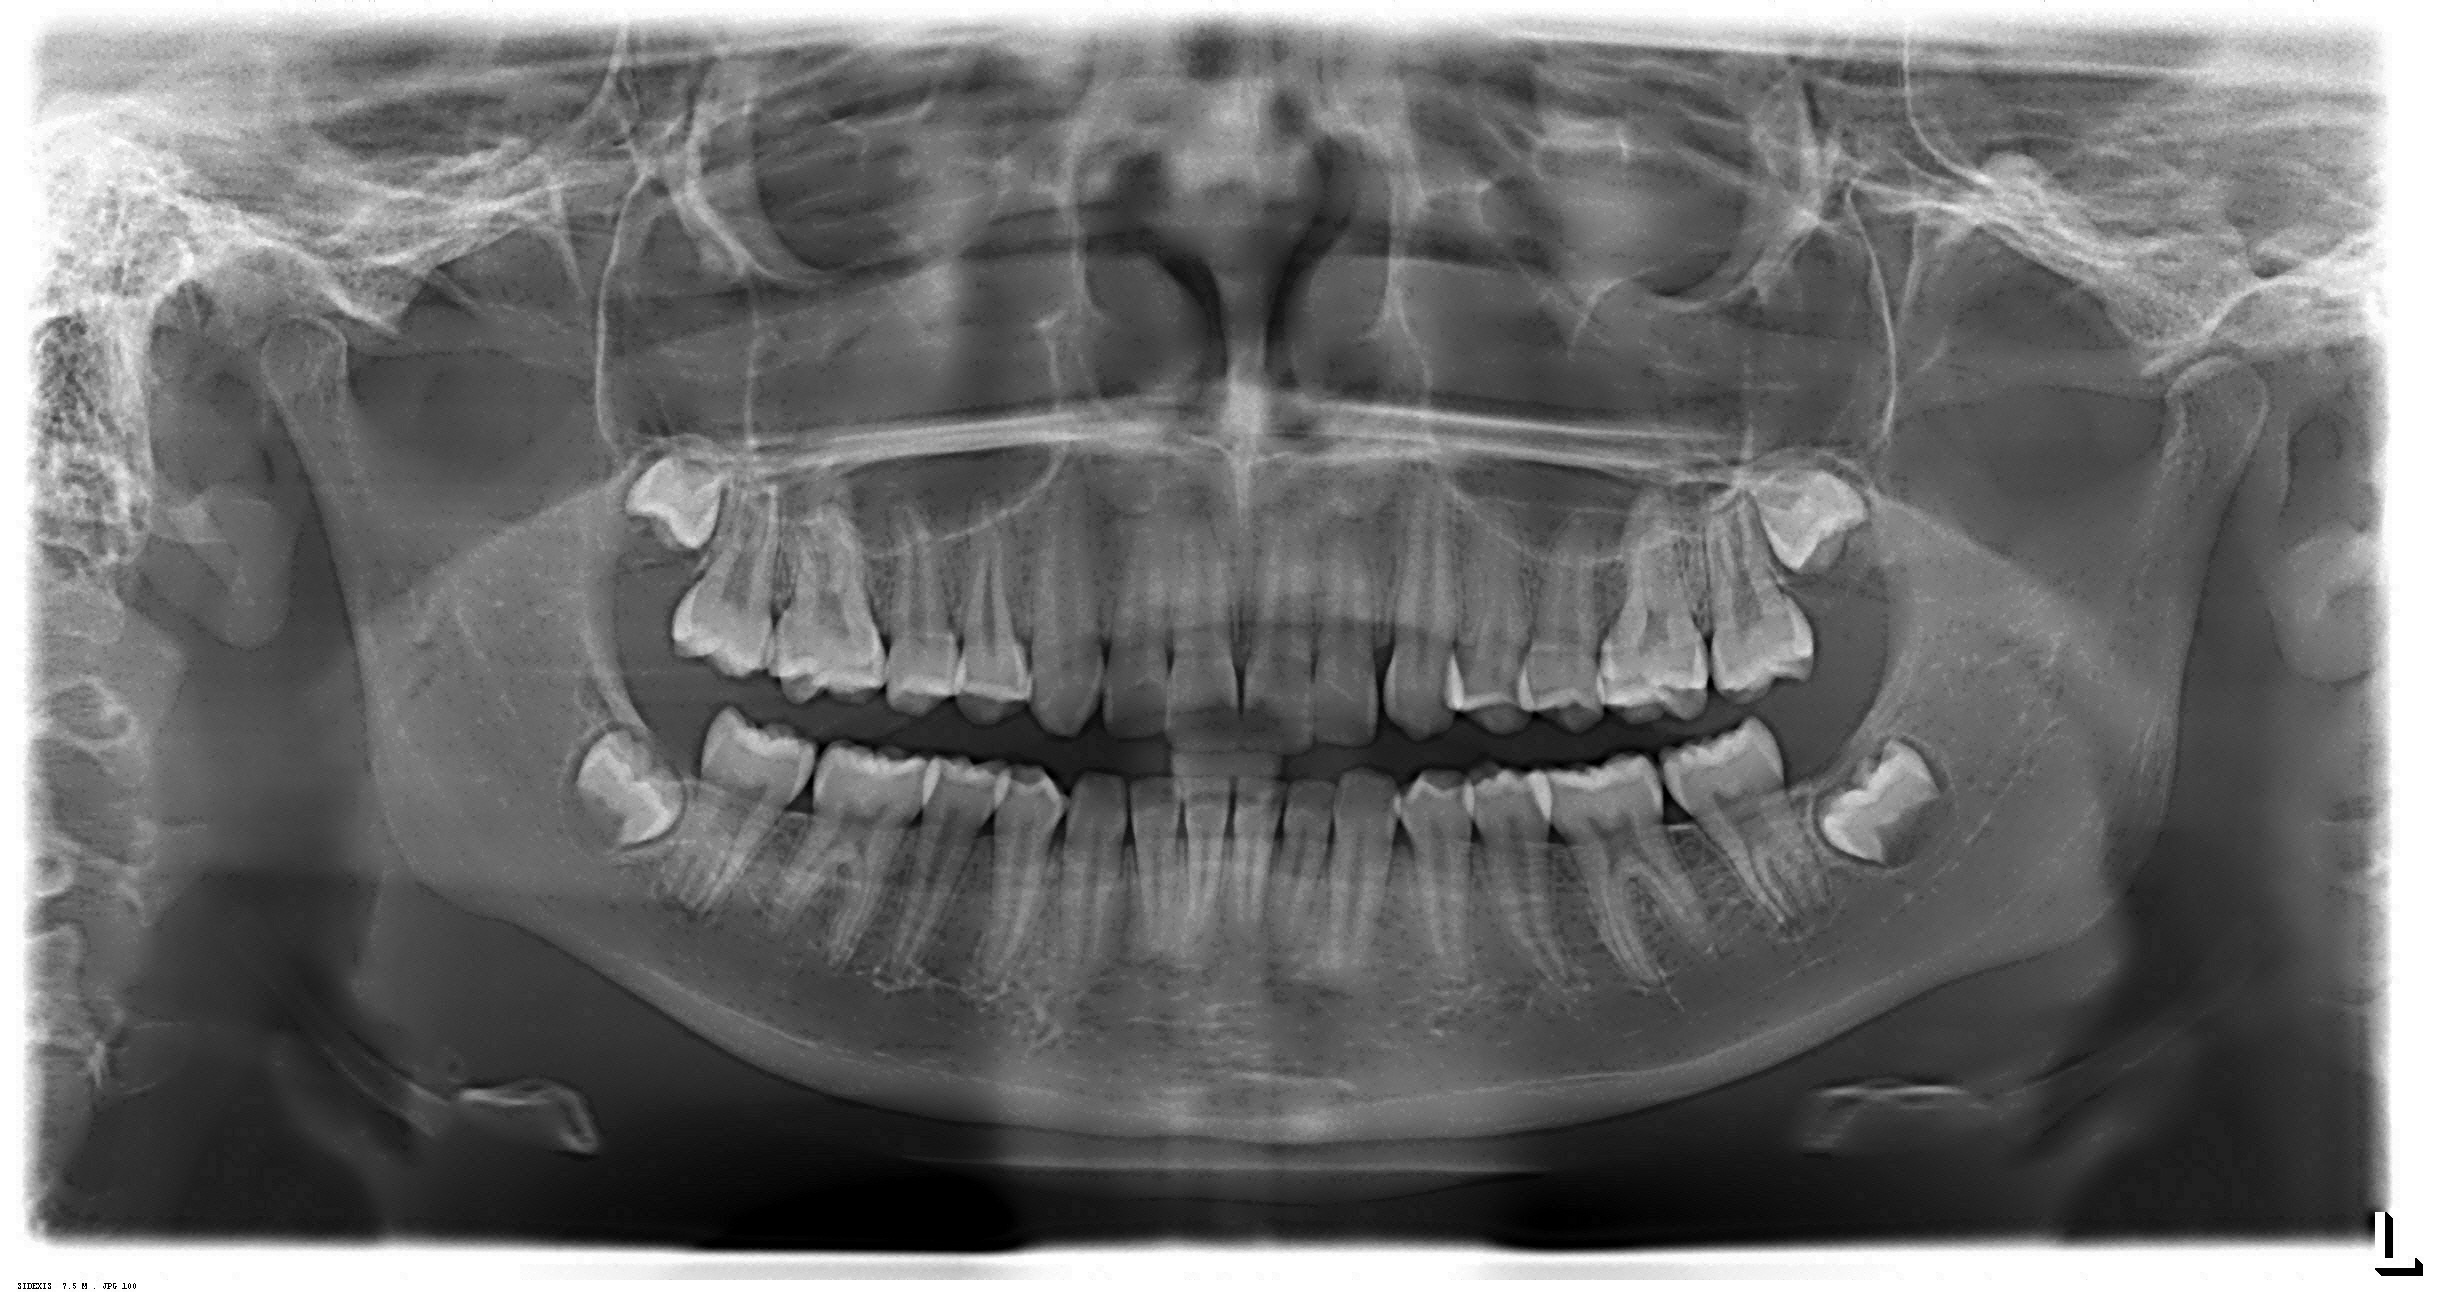

Radiografias Digitais

- Raio X Panorâmico